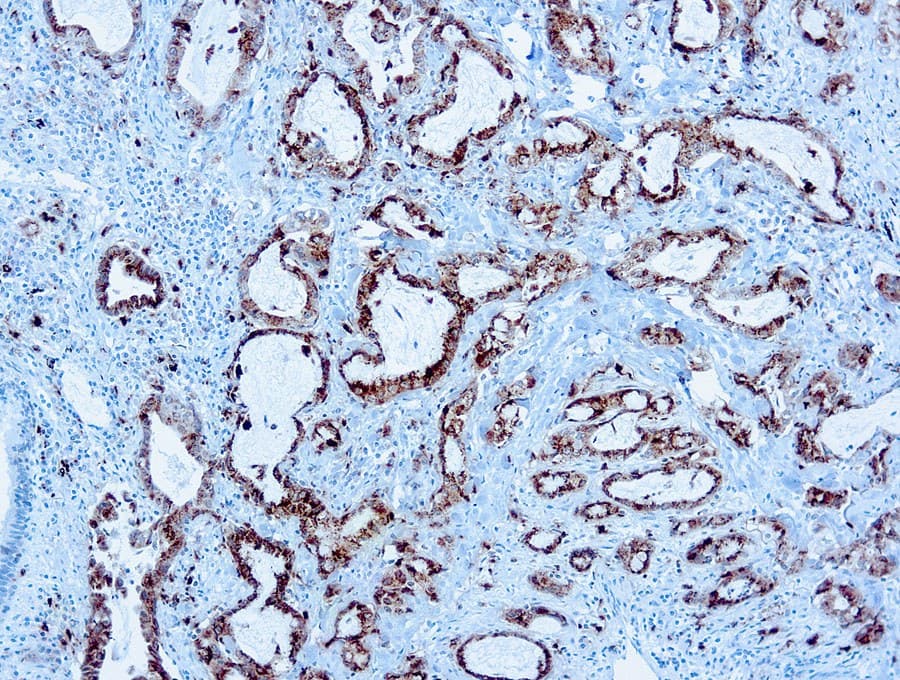

- Detecta una tinción granular citoplasmática asociada con la diferenciación de células alveolares tipo II.

- Utilizados como parte de paneles diagnósticos para la clasificación del adenocarcinoma de pulmón y el diagnóstico diferencial de tumores pulmonares frente a metastásicos.